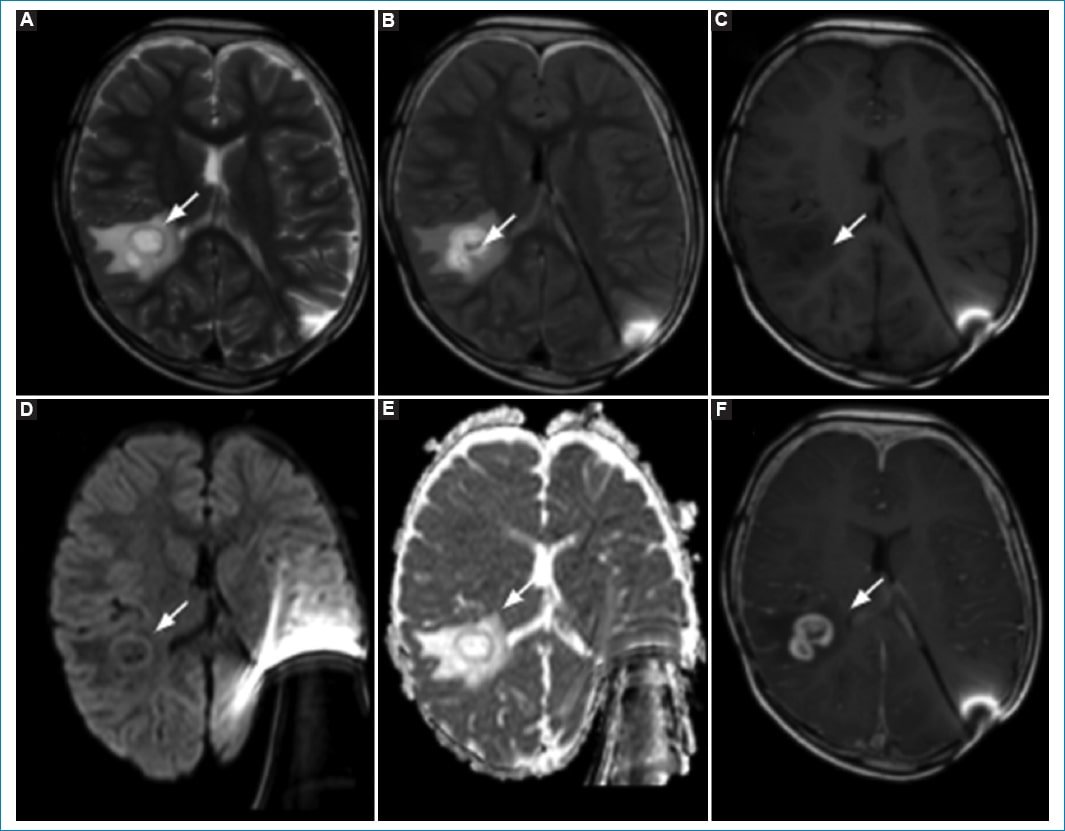

En la RM de control, cuatro años después de la finalización del tratamiento (2022), se observa una lesión focal en la sustancia blanca lobular temporal posterior derecha cuyo centro muestra señal isointensa con el líquido cefalorraquídeo (LCR) sin restricción en DWI, cuya pared es sutilmente hipointensa ponderada en T2 e hiperintensa en T1. Presenta refuerzo anular tras la administración de contraste intravenoso, con discreta nodularidad en su margen interno, y edema vasogénico perilesional con leve colapso del cuerno posterior del ventrículo lateral homolateral. Mide aproximadamente 16 × 12 mm. Se sospecha una lesión de probable origen infeccioso (Fig. 2).

Figura 2. RM de control seis años después de la exéresis de la lesión primaria, donde se observa una lesión focal en la sustancia blanca temporal posterior derecha, cuya pared es sutilmente hipointensa ponderada en T2 (A) e hiperintensa en T1 (B), y (C) el centro muestra señal isointensa con el LCR sin restricción a la difusión (D y E). Presenta refuerzo anular tras la administración de contraste intravenoso (F), con discreta nodularidad en su margen interno.

Se realizó biopsia de la lesión, obteniendo un diagnóstico histopatológico de glioma difuso de alto grado de tipo pediátrico IDH de tipo salvaje, H3 de tipo salvaje, amplificación C-MYC y N-MYC negativa, grado IV de la WHO (2021) (Fig. 3).

Figura 3. RM de control a los tres meses del último control, donde observa progresión con mayor confluencia de las anomalías de señal en T2(A)-FLAIR (A y B) del parénquima temporal posterior derecho, actualmente con imagen quística de márgenes engrosados irregulares hiperintensos en T1 (C) con leve restricción de la difusión de la pared (D y E) y realce en anillo poscontraste intravenoso (F).